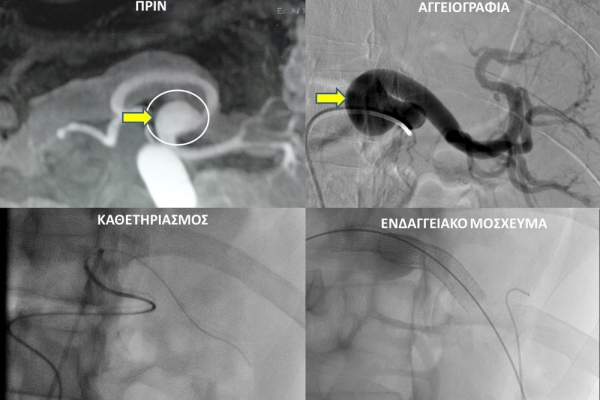

Ο επεμβατικός ακτινολόγος θα προσεγγίσει το παθολογικό αγγείο ενδοαυλικά και με απεικονιστική καθοδήγηση θα τοποθετήσει τακατάλληλα υλικά αποκατάστασης του ανευρύσματος. Υπάρχουν μια σειρά από επιλογές θεραπείας και η θεραπεία, που θα επιλεχθεί, εξαρτάται από την τοποθεσία και το σχήμα του ανευρύσματος.Μία πιθανή επιλογή για ενδαγγειακή θεραπεία περιφερικής αρτηρίας είναι η χρήση ενδαγγειακού μοσχεύματος stent-graft. Εναλλακτικά, το εσωτερικό του ανευρύσματος μπορεί να γεμίσει με εμβολικό υλικό (μικρά σπειράματα-coils ή ειδικη κόλλα), το οποίο εμποδίζει την ροή αίματος στο ανεύρυσμα.